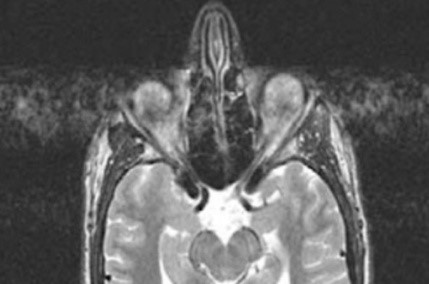

Którą strukturę anatomiczną oznaczono na obrazie rezonansu magnetycznego?

Ilustracja do pytania 15

A. Trzon kości ramiennej.

B. Guzek większy kości ramiennej.

C. Głowę kości ramiennej.

D. Guzek mniejszy kości ramiennej.